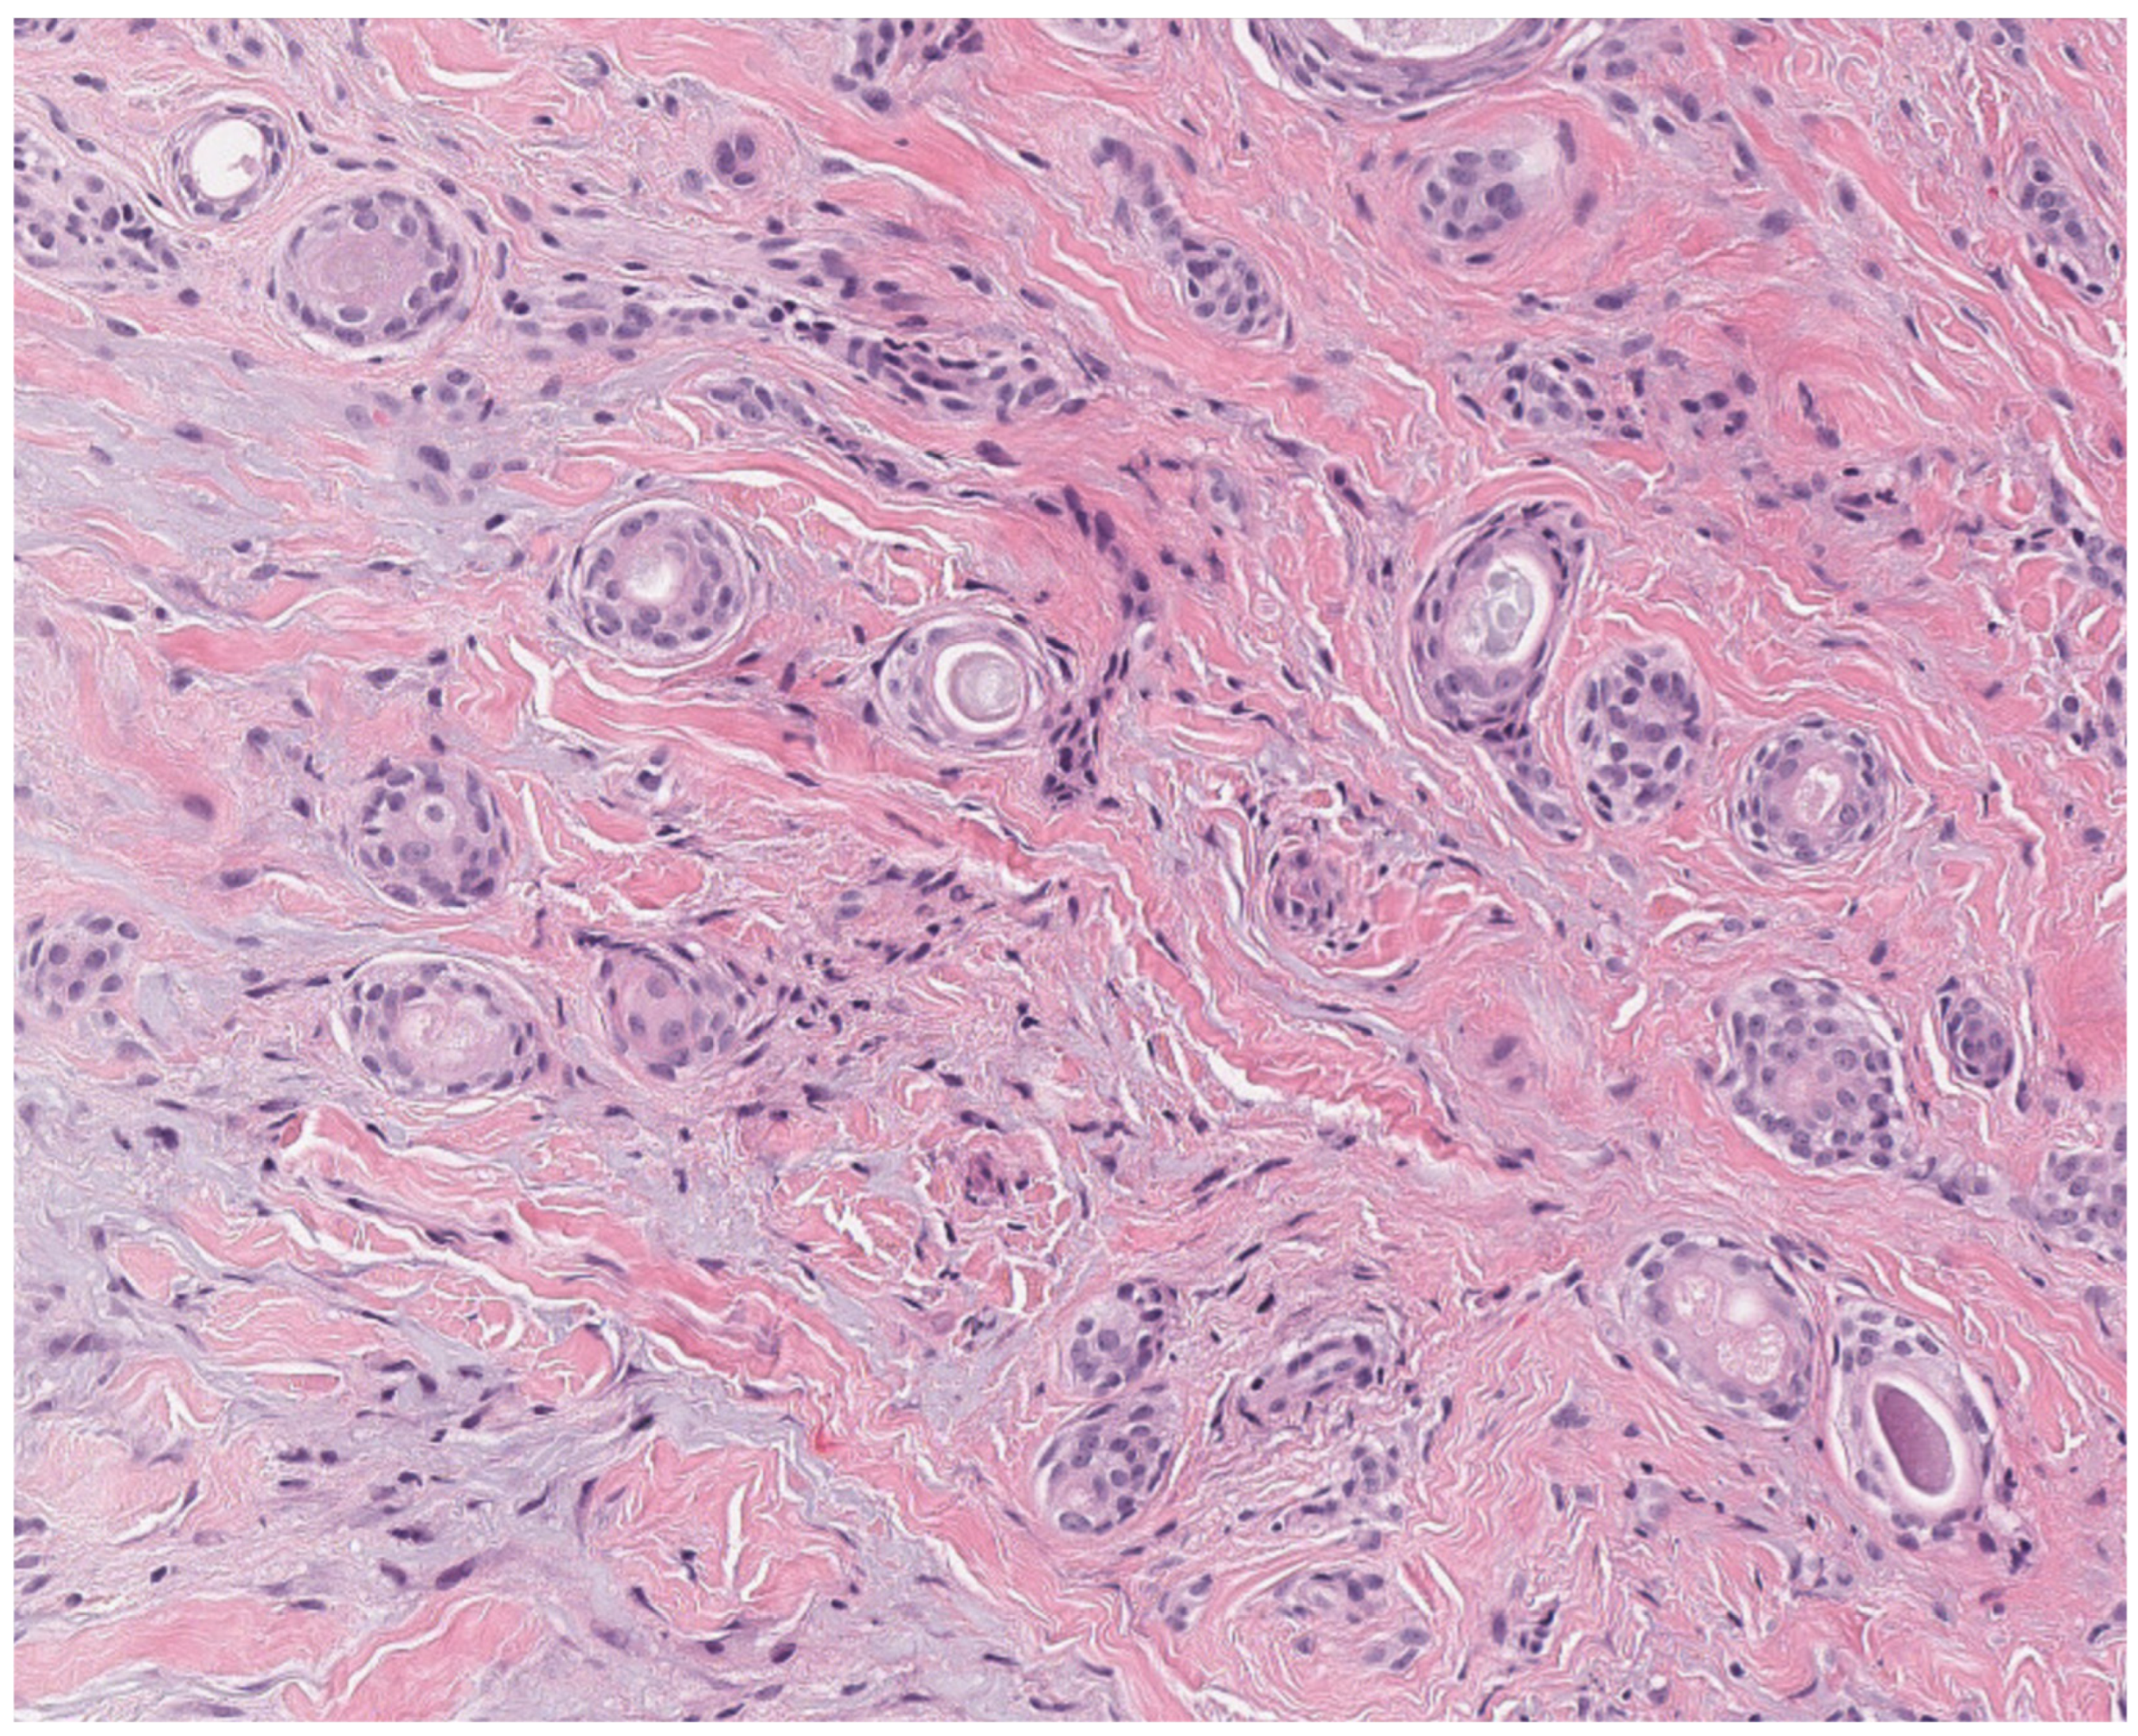

2.3. Pilomatricoma